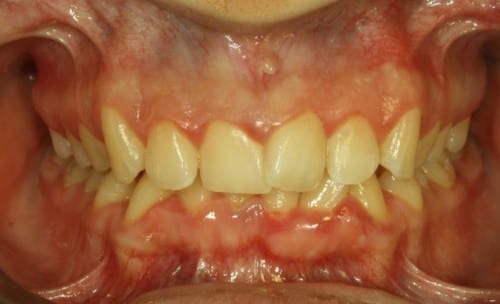

Paciente con brackets cerámicos de autoligado Clarity SL, de la empresa 3M. Hoy en día, una de las mejores y más estéticas opciones del mercado en Ortodoncia «por fuera».

Vista de cerca de los brackets Clarity SL, el sistema de autoligado de la compañía 3M

Hablaremos al detalle de ellos en otras entradas, mientras tanto, os dejo unas fotos, para que veáis la tecnología Smart Clip y la posibilidad de que dichos brackets autoligables sean cerámicos: su nombre comercial es Brackets Clarity SL (del inglés, Self-Ligation, autoligado).